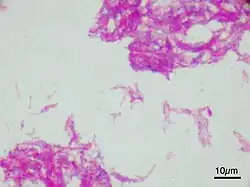

Microscopic image of the Calmette–Guérin bacillus, Ziehl–Neelsen stain, magnification: 1,000nn | |